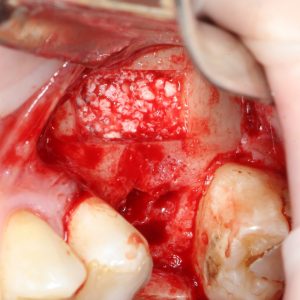

Пришло время вернуться к синуслифтингу и заполнить сформированное ранее субантральное пространство графтом (Geistlich Bio-Oss Pen):

запечатываем заполненное субантральное пространство:

Как это правильно сделать, читайте здесь>>, здесь>> и здесь>>.